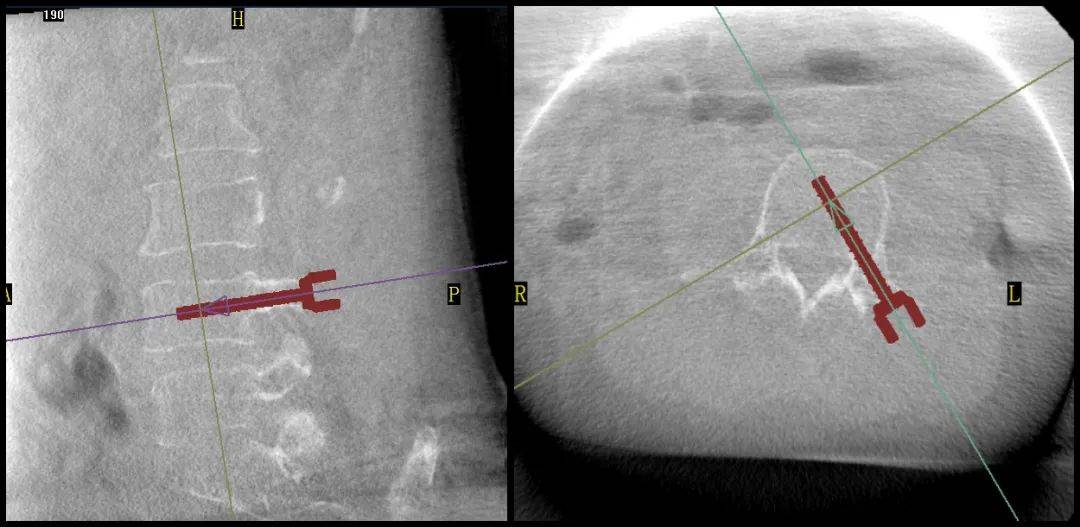

手術(shù)過程中,普愛醫(yī)療平板三維C形臂為患者拍攝了清晰的三維影像,醫(yī)生基于影像完成了兩個節(jié)段的穿刺路徑規(guī)劃。

普愛醫(yī)療品牌骨科手術(shù)機(jī)器人的機(jī)械臂憑借高精度導(dǎo)航能力,引導(dǎo)醫(yī)生一次性精準(zhǔn)穿刺,憑借超大內(nèi)傾角度單通道抵達(dá)椎體中央位置,達(dá)到雙通道的骨水泥彌散效果,成功完成兩節(jié)跨節(jié)段椎體的骨水泥注入。